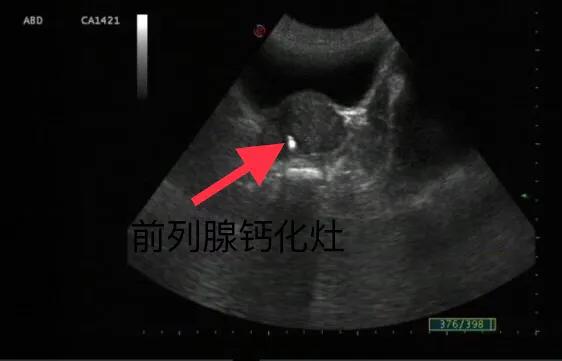

B超操作简便,无损伤,可重复性强,是目前临床诊断前列腺钙化灶的首选和常用方法。

前列腺结石就是常说的前列腺钙化灶,B超超声检查显示前列腺内有较小的单发或者多发的强回声。